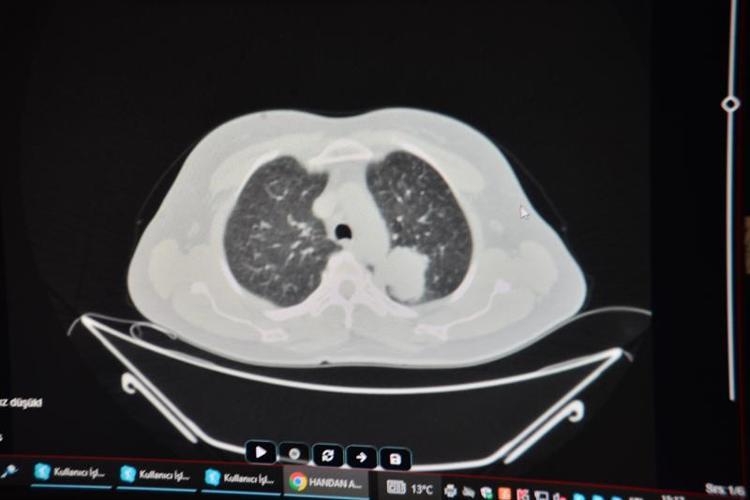

Adana'da göğüs ağrısı ve öksürük şikayetleriyle başvurduğu hastanede yapılan ileri tetkiklerde akciğerinde kitle saptanan ev kadını Handan Aras'a (55) Balcalı Hastanesi Göğüs Cerrahi Bölümü'nde akciğer kanseri teşhisi kondu. Doç. Dr. Alper Avcı ve ekibi tarafından ameliyat edilen Aras'ın akciğerindeki tümörlü doku alındı. Kısa sürede sağlığına kavuşan Aras, "Çok sigara kullanan biriydim. Ameliyat olduğumdan beri hiç içmedim. 30 yıl sigara içtim ama artık kullanmayı düşünmüyorum. Bu kadar acıyı yaşadıktan sonra imkansız. Kimse benim gibi bir hata yapsın istemiyorum" dedi.

Yakın zamana kadar büyük çoğunlukla erkeklerde görülen akciğer kanserinin son yıllarda özellikle kadınlarda sigara kullanımına bağlı olarak artışa geçtiğine dikkati çeken ÇÜ Tıp Fakültesi Balcalı Hastanesi Göğüs Cerrahi Anabilim Dalı Öğretim Üyesi Doç. Dr. Alper Avcı, "Hastamız da sigara içen bir gruptandı. Yaptığımız ameliyatla tümörü tüm dokusuyla birlikte temizleyebilmek adına sol akciğer üst lobunu almak durumunda kaldık.

Bölgede tümörün yayılma ihtimali olan lenf bezelerinin de hepsini topladık. Şu an durumu gayet iyi ve onkolojik tedavisi devam ediyor. Son yıllarda akciğer kanseri kadınların sigara içme alışkanlıklarının değişmesine bağlı olarak bu grupta ciddi anlamda artış gösterdi. Ülkemizde, kadınlarda akciğer kanseri görülme durumu diğer kanserlere göre 4’üncü sıraya kadar yükseldi. Yani yüzde 10'ların bile altında olan görülme sıklığı, yüzde 15-20'lere tırmandı" diye konuştu.

Detaylı radyolojik incelemeler sonucunda akciğerinde bir kitle olduğu ortaya çıkıyor. Daha sonra onun tanısı ve tedavi planlaması yapılıyor. Kesinlikle sigaradan uzak durulmasını tavsiye ediyoruz. Zira sigara her halükarda akciğer kanserinin temelinde ispatlanabilmiş en bariz etkendir" ifadelerini kullandı.